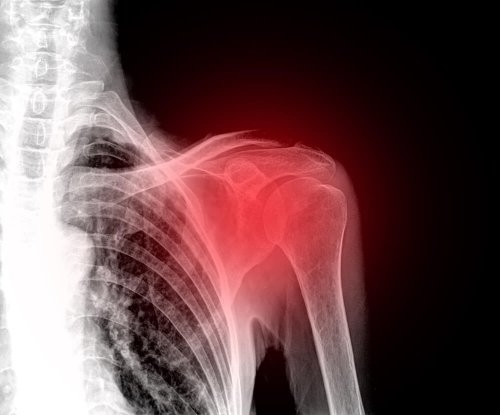

L’épaule gelée est une affection traumatique de l’épaule. Cette affection est également connue sous le nom de “capsulite rétractile” dû au fait que l’inflammation de la capsule articulaire de l’épaule soit le mécanisme de production final des symptômes.

Pour comprendre cela, il est nécessaire de connaître la structure de l’épaule. L’épaule est une articulation dans laquelle trois os sont en contact, à savoir l’humérus, la clavicule et l’omoplate ; du tissu mou recouvre ces os formant ainsi une capsule. Cette capsule s’épaissit lorsque l’on souffre d’épaule gelée.